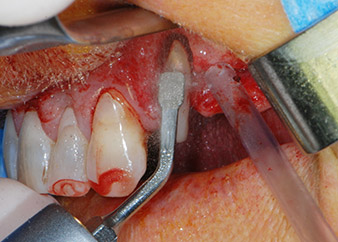

Bone deficiencies around the implants, at the mesial aspect of tooth 27 and around the buccal root of tooth 24, were filled with xenogeneic bone substitute particles and covered with an absorbable collagen membrane (Bio-Gide, Geistlich Biomaterials) for GBR augmentation (Figs. 13 and 14).

Xenogeneic bone substitute material

Fig. 13: Xenogeneic bone substitute material was used to fill the remaining osseous defects …

absorbable collagen membrane

Fig. 14: ... which was then covered with an absorbable collagen membrane. The grayish-pink structure between the elevators at the top margin of the picture represents interproximal papillary tissue.

Finally, after periosteal incision, the site was passively sutured with a coronally advanced flap, using 5-0 absorbable suture material (Fig. 15). The postoperative radiograph showed both implants in their correct vertical position (Fig. 16).